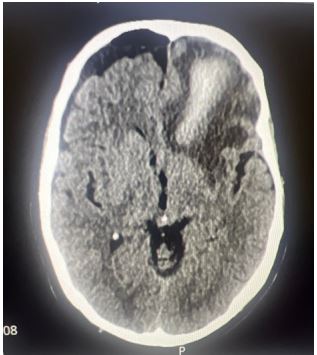

A 75-year-old man underwent elective bilateral revision FESS for recurrent right-sided nasal polyps. His history included a previous FESS in 2014 and burr hole drainage of a chronic subdural haematoma in 2019. Initial recovery was unremarkable. On the evening of surgery, he became confused, vomited coffee-ground emesis, and was noted to have right- sided weakness and facial droop. GCS was E4V4M6, BP elevated at 230/120 mmHg. A CT brain showed a left frontal intracerebral haemorrhage with pneumocephalus and a suspected breach of the ethmoid sinus.

Figure 2: Follow-up CT showing reduced pneumocephalus and improving mass effect.